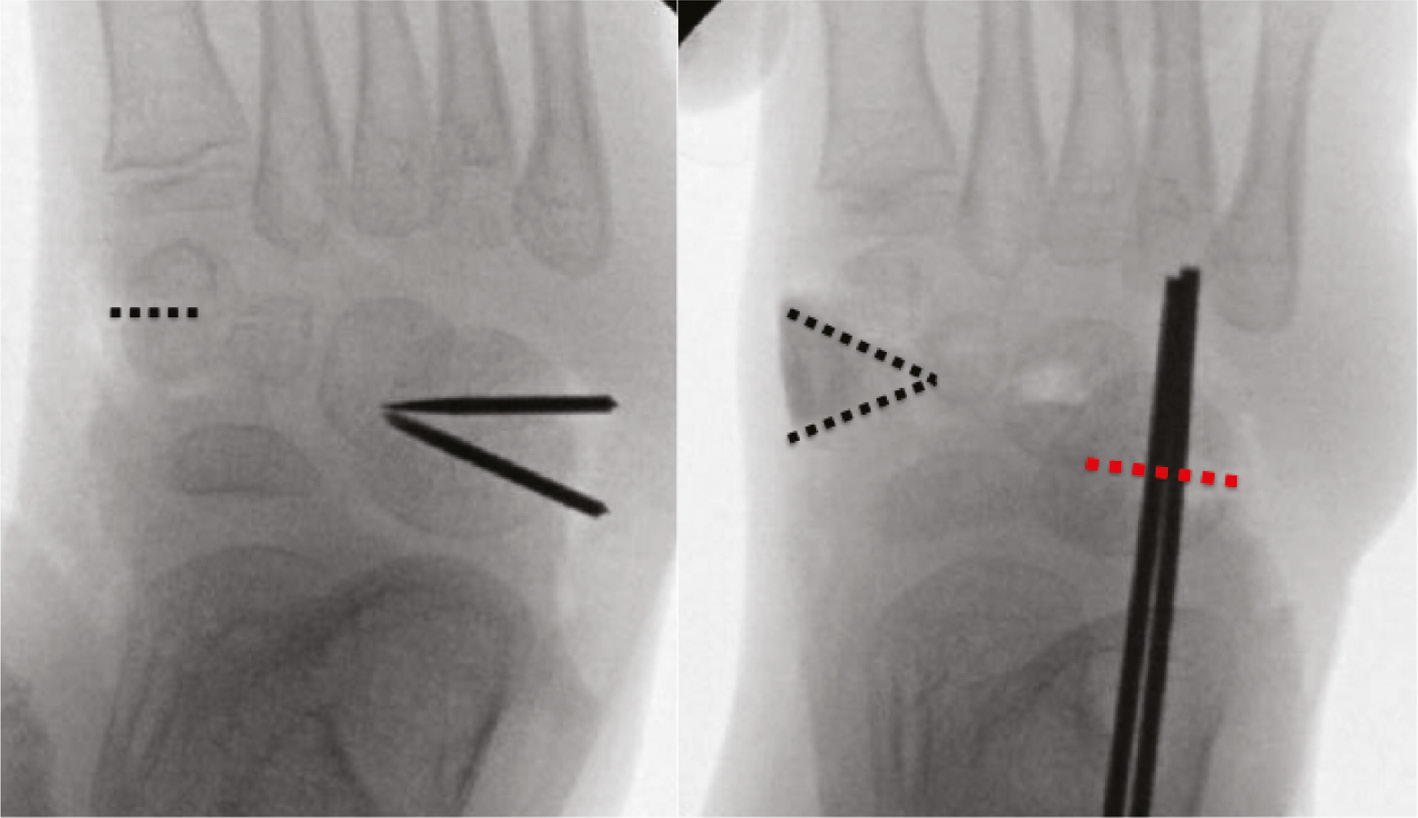

Talonavicular pins can be used in pediatric vertical talus foot deformity or clubfoot surgery for those patients who have failed Ponseti casting. Pin fixation may be used in calcaneal neck lengthening procedures. In older children, larger pins may be used to yield a lateral closing wedge valgus-producing osteotomy in addition to calcaneal neck lengthening. Pins can also be used as guides to precisely orient cuts by using them as intraosseous saw guides.

Pins are utilized to a great degree in foot surgery as a means to effect correction (Figure 17) and to stabilize the foot while it heals.

In general, smooth pins are used to stabilize opening wedge osteotomies as they can be removed in clinic without sedation. Threaded pins are needed for closing wedge osteotomies as they can keep the bone edges opposed; unfortunately, these need removal in the operating room (Figure 18).

Figure 18. A five-year-old with a history of clubfoot and with residual metatarsus adductus underwent opening wedge osteotomy of the first cuneiform with allograft. A closing wedge cuboid osteotomy was planned with smooth K-wires as interosseus guides and the osteotomy was held closed with threaded K-wires.